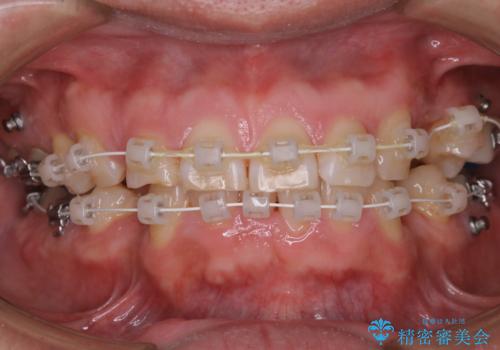

表のワイヤー装置で矯正中にPMTCで綺麗にお掃除

担当医 歯科衛生士